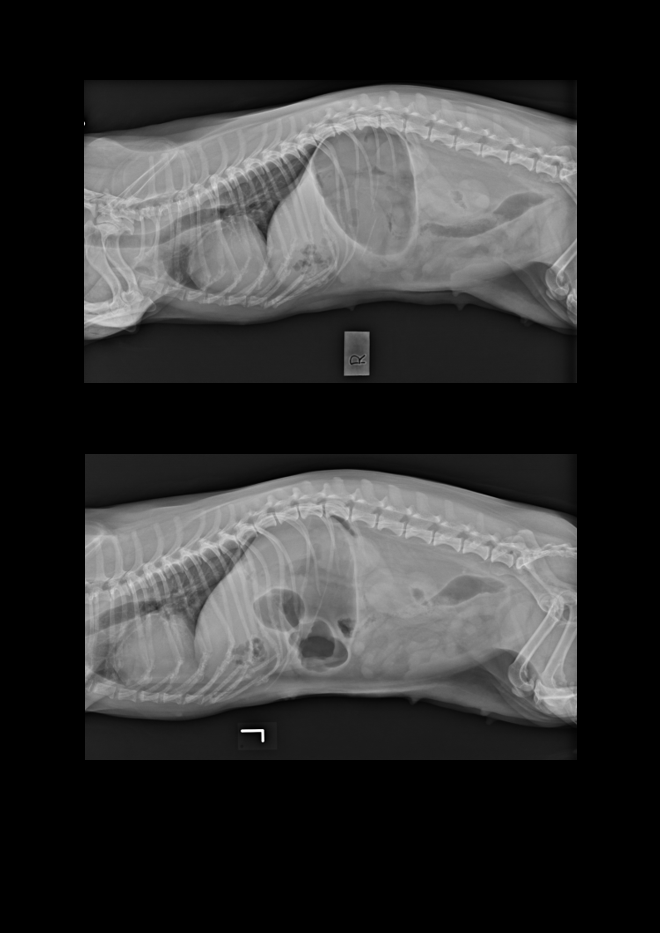

Signalement: Dachs, tispe, 11 år Anamnese: Mistanke magedreining